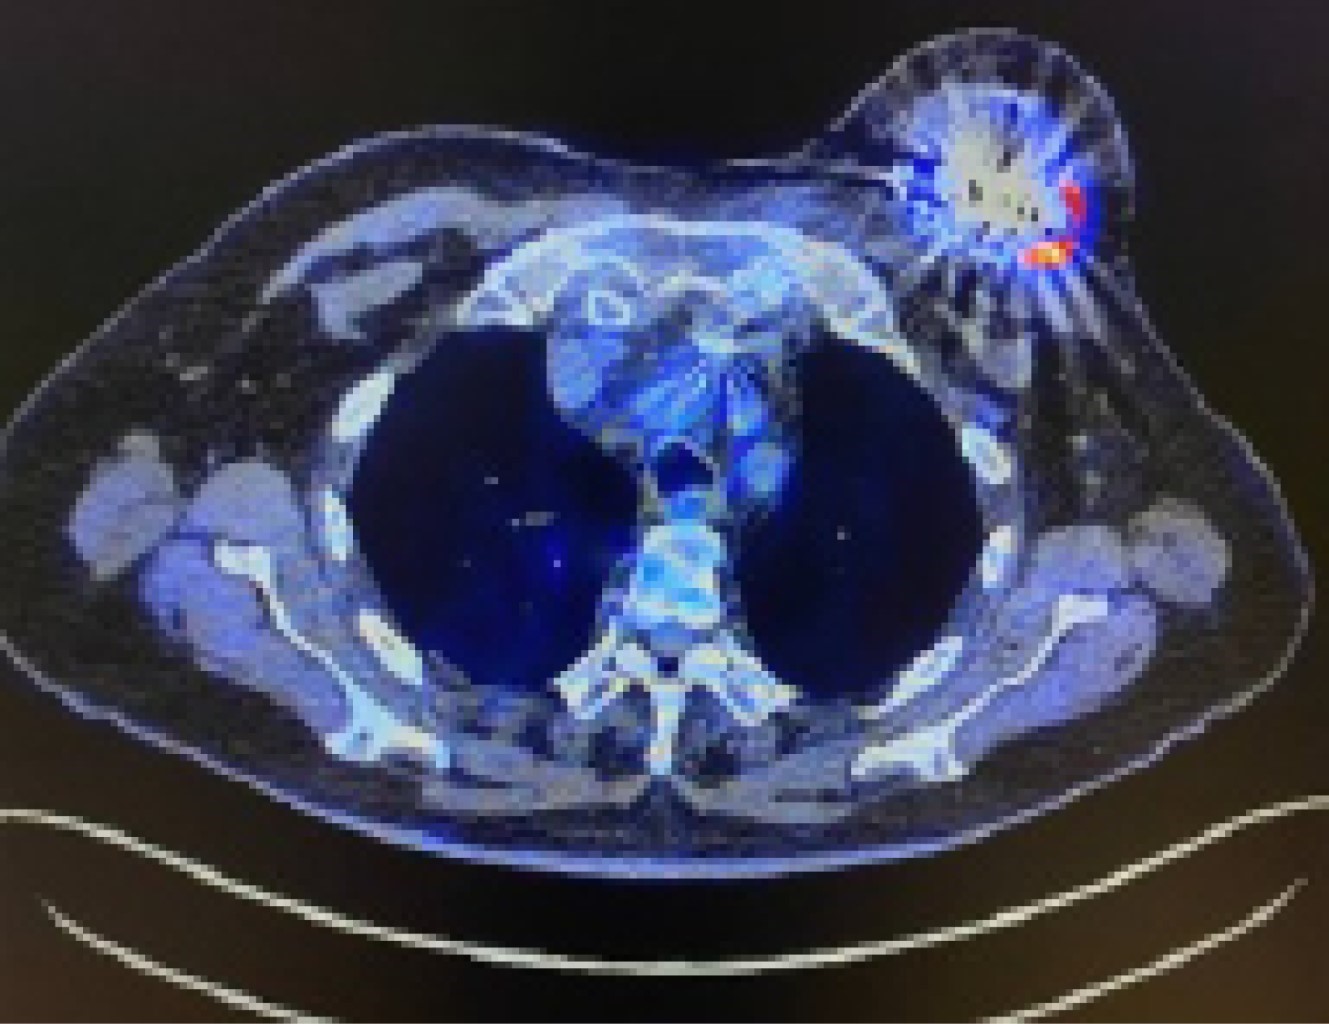

Figura 1

Figura 2

Figura 3